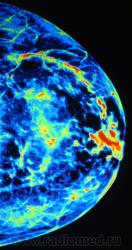

Возможности "цветовой" обработки цифрового изображения молочной железы.